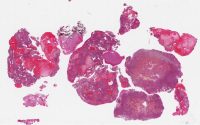

CANP2008-1.svs

60000 x 37785

@ 20X